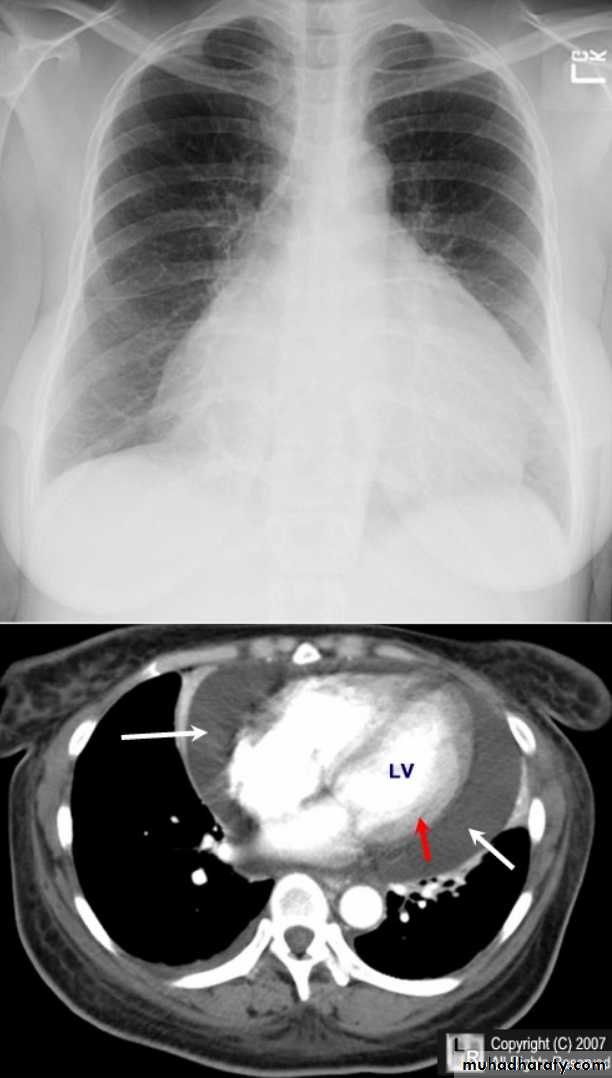

Pericardial effusions occur when fluid collects in the pericardial space (a normal pericardial sac contains approximately 30-50 mL of fluid).

adiographic features

Plain radiograph

a very small pericardial effusion can be occult on plain film

there can be globular enlargement of the cardiac shadow giving a water bottle configuration known as Globe shape heart or pumpkin shape heart .

Pericardial effusion